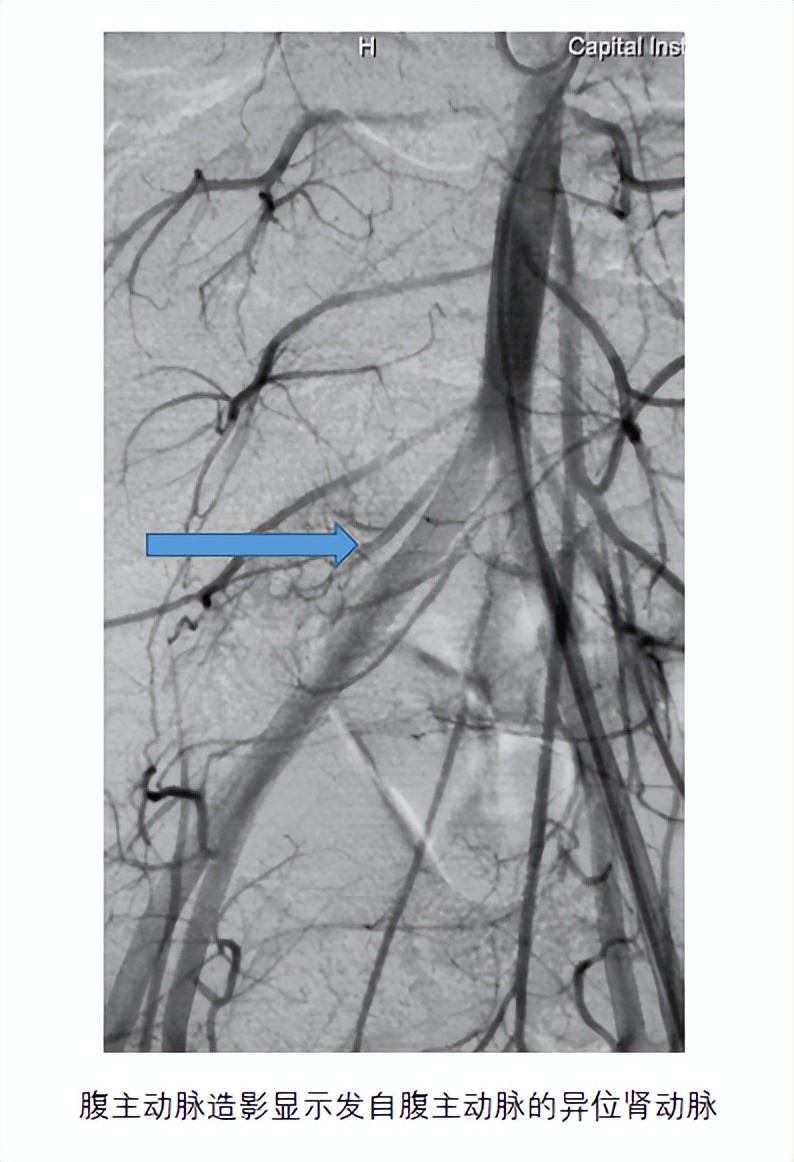

患儿做完手术前检查,无明显治疗禁忌,先行腹主动脉造影显示发自腹主动脉的异位肾动脉,微导管超选择入异位肾动脉,注入微球及弹簧圈行栓塞。栓塞后孩子无不适,第二天遗尿症状明显缓解。患儿妈妈的脸上也露出了久违的笑容。查完房后,办理出院。